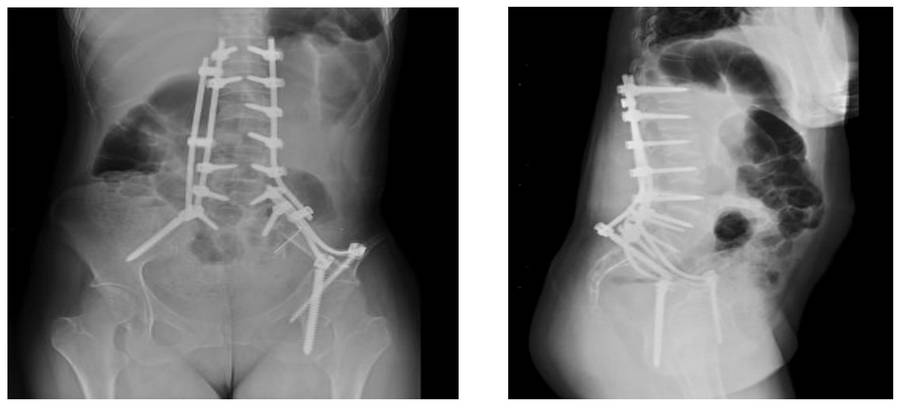

- The patient underwent successful two-level decompression, partial corpectomy, cementation, and lumbopelvic fixation for pathological fractures of the 2nd and 3rd lumbar vertebrae, epidural and root compression.

Post-surgery: The X-ray shows cementation and lumbopelvic fixation following partial laminectomy and corpectomy.